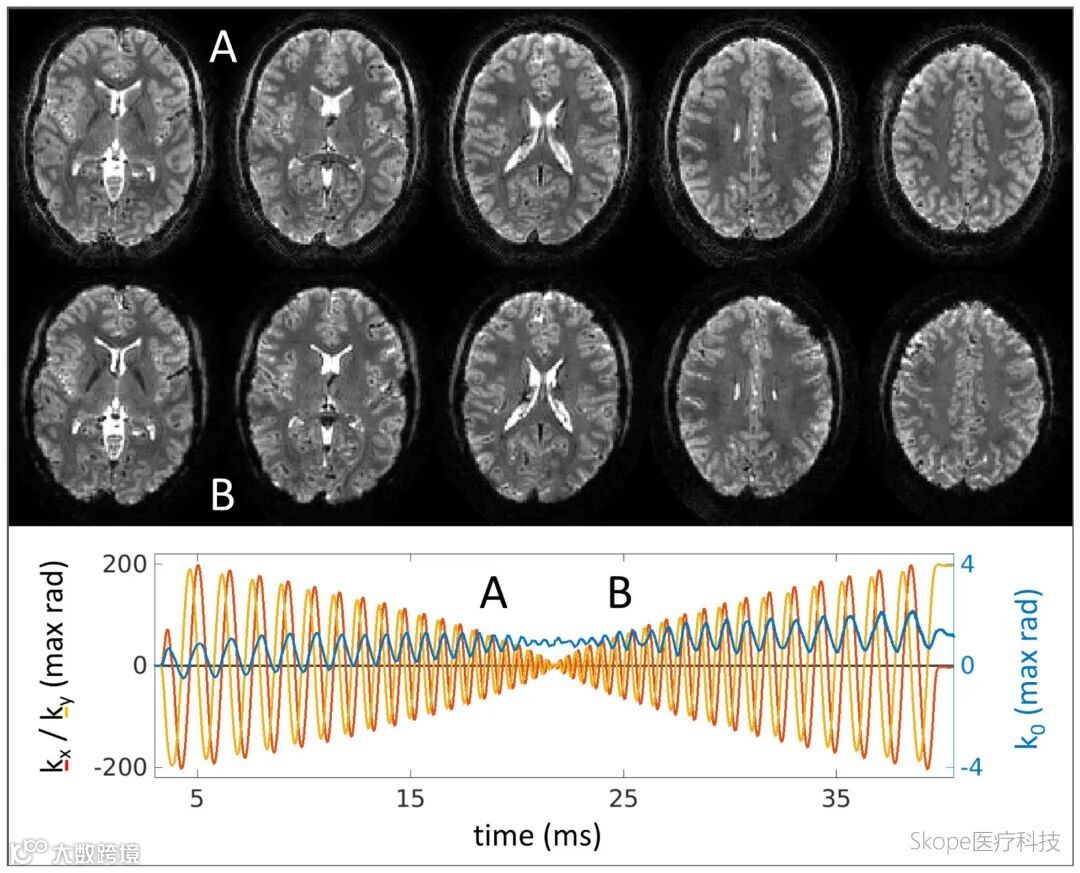

半激发(half-shot)螺旋采集展现多图像能力

spiral-in-out与out-in方案可在一次激发后获取两个不同TE下的图像,拓展了多对比采集可能性。实验证明,spiral-in-out在保持整体对比度的同时,能通过后段采集获取更清晰的脑脊液与白质边界;spiral-out-in则提供短TE与长TE图像对比,有助于脂肪抑制及结构保持,两者各具优势。

螺旋out in成像结果。每个切面两幅图像,短TE图像显示部分脂肪残留,长TE图像几何结构稳定。